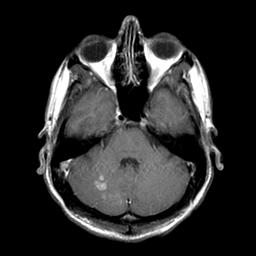

Sarcoma, MR Study #1 mr-gad -- Slice #5

[Home][Help][Clinical] Slice 5